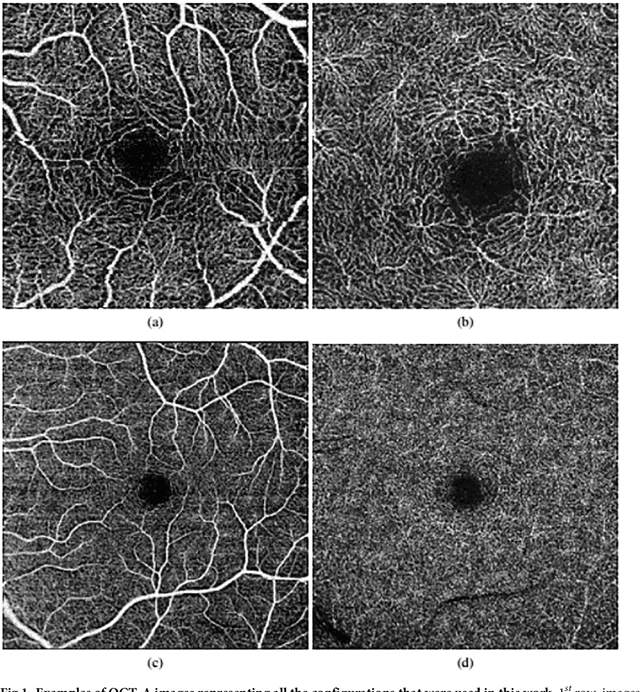

Abstract:Angiography by Optical Coherence Tomography is a non-invasive retinal imaging modality of recent appearance that allows the visualization of the vascular structure at predefined depths based on the detection of the blood movement. OCT-A images constitute a suitable scenario to analyse the retinal vascular properties of regions of interest, measuring the characteristics of the foveal vascular and avascular zones. Extracted parameters of this region can be used as prognostic factors that determine if the patient suffers from certain pathologies, indicating the associated pathological degree. The manual extraction of these biomedical parameters is a long, tedious and subjective process, introducing a significant intra and inter-expert variability, which penalizes the utility of the measurements. In addition, the absence of tools that automatically facilitate these calculations encourages the creation of computer-aided diagnosis frameworks that ease the doctor's work, increasing their productivity and making viable the use of this type of vascular biomarkers. We propose a fully automatic system that identifies and precisely segments the region of the foveal avascular zone (FAZ) using a novel ophthalmological image modality as is OCT-A. The system combines different image processing techniques to firstly identify the region where the FAZ is contained and, secondly, proceed with the extraction of its precise contour. The system was validated using a representative set of 168 OCT-A images, providing accurate results with the best correlation with the manual measurements of two experts clinician of 0.93 as well as a Jaccard's index of 0.82 of the best experimental case. This tool provides an accurate FAZ measurement with the desired objectivity and reproducibility, being very useful for the analysis of relevant vascular diseases through the study of the retinal microcirculation.